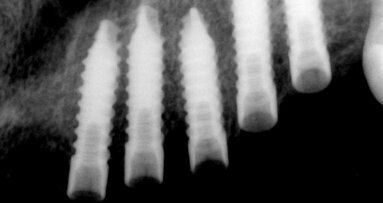

Do naší ordinace se dostavila 33letá pacientka s žádostí o výměnu starých, nevyhovujících amalgámových výplní a inlejí v esteticky významné oblasti za „neviditelné“ výplně. Po vyšetření klinického stavu, vyhodnocení bitewing RTG snímku a detailní prohlídce bylo rozhodnuto, že se amalgámové výplně a inleje z NDK (slitiny náhradního kovu) v horních premolárech (obr. 1 a 9) nahradí výplněmi kompozitními. Protože klinické ani rentgenologické vyšetření nenasvědčovalo pravděpodobnosti komplikací, bylo možné rekonstruovat oba kvadranty současně během jedné návštěvy ordinace.